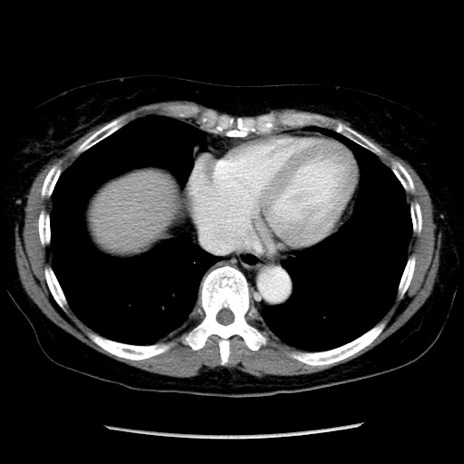

症例6(横断像)

【症例】50歳代女性

【主訴】下腹部痛

【現病歴】本日朝より下痢2回あり。 昼食を食べた後、嘔吐3回、下腹部痛認め、症状軽快せず、当院救急搬送。

【既往歴】卵巣癌術後(8年前に当院で卵巣摘出)

【身体所見】 意識清明、腹部:平坦、腸蠕動音→、やや硬、下腹部自発痛・圧痛あり、反跳痛あり、筋性防御なし。

【データ】WBC 16000、CRP 0.01